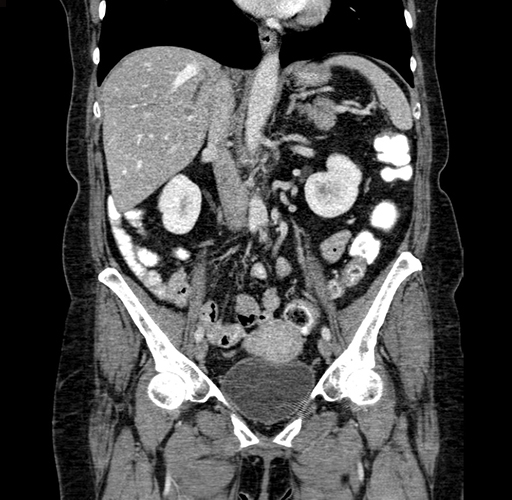

Coronal Venous